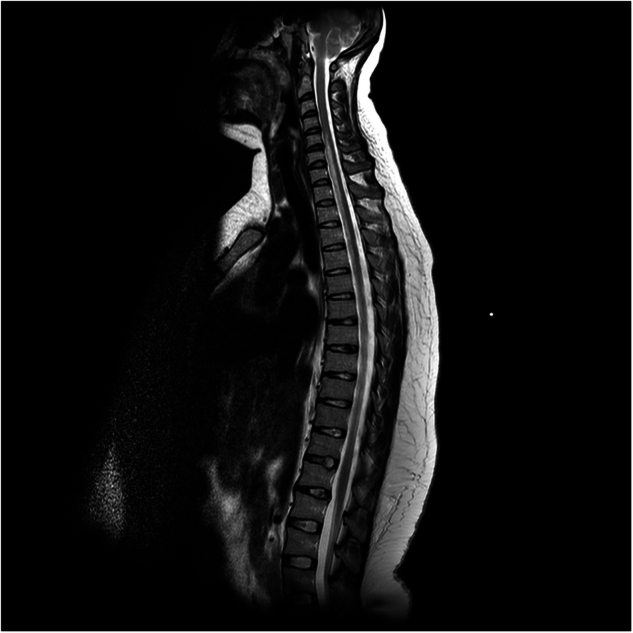

Case presentation: A 28-year-old female presented at 16 weeks gestation with chest and back pain and paraesthesia in her fingers. Magnetic resonance imaging on admission revealed a spinal cord lesion extending from C5-T8. She was treated with anticoagulation and rehabilitation. Six years following presentation she was able to return to work. A 42-year-old male experiencing central chest pain and leg weakness was initially diagnosed as having acute coronary syndrome. Following discharge, he was re-admitted with urinary retention and leg weakness. Magnetic resonance imaging revealed a spinal cord lesion extending from T4 to T7. He was treated with anticoagulation, and eight months following presentation he regained full muscle strength but required intermittent self-catherisation. Three further cases are described.